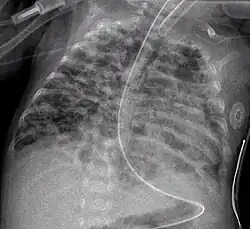

Вторая стадия (4—10-й дни жизни) — ателектазы становятся более распро страненными и чередуются с участками эмфиземы, участки некрозов и репарации эпителия бронхиол, некротические массы заполняют воздухоносные пути. На рентгенограмме грудной клетки — «воздушная бронхограмма», легочные поля местами затемнены, но видны участки интерстициальной эмфиземы;

Третья стадия (11—З0-й дни жизни) — распространенная метаплазия и гиперплазия эпителия бронхов и бронхиол, участки эмфиземы, окруженные зонами ателектаза, массивный интерстициальный фиброз и отек с истончением базальных мембран, альвеол. На рентгенограмме — участки воспаления, зоны ателектазов и появление кист;

Четвертая стадия (2 месяц жизни) — массивный фиброз легких с деструкцией альвеол и стенок воздухоносных путей (с метаплазией эпителия), гипертрофия мышечного слоя бронхиол, уменьшение количества легочных артериол и капилляров с гипертрофией мышечного слоя артериол и венул. На рентгенограмме — массивный фиброз легких с отеком и зонами воспаления, уплотнений.

Начальные стадии БЛД характеризуются тем, что обычно у недоношенного ребенка при проведении ИВЛ по поводу СДР не удается через неделю «уйти» от жестких параметров ИВЛ, «зависимости» от высоких величин FiO2- При попытке уменьшить инспираторное давление (PIP) или снизить концентрацию кислорода во вдыхаемой кислородно-воздушной смеси (Fio2 ) развивается дыхательная недостаточность с гипоксемией и гиперкапнией. Необходимость высокого PIP обусловлена повреждением и деструкцией воздухоносных путей, уменьшением легочной растяжимости из-за фиброза и потери эластических волокон. Зависимость от высокого Fio2 связана с гибелью, снижением количества легочных капилляров и артериол, нарушениями капиллярно-альвеолярного обмена газов при фиброзе интерстиция, отеке легочной ткани. Грудная клетка у ребенка приобретает бочкообразную форму, вздута, увеличен ее переднезадний размер (при СДР I типа она имеет вид «спичечного коробка»), имеется втяжение межреберий при дыхании. Отмечается одышка с затруднением выдоха, хрипами на выдохе; может быть и стридор. Однако для детей с БЛД типич- ны и приступы апноэ с брадикардией. Кожные покровы обычно бледные с циано- тичным оттенком. Показатели Ро2 в крови у этих детей в первом полугодии жизни остаются сниженными, нередко достигая 45—50 торр (мм рт.ст.). Обращает на себя внимание стойкость рентгенологической картины легких в виде чередования участков пониженной прозрачности легочной ткани, чаще среднемедиальных от- делов, грубого интерстициального рисунка (фиброза) и участков гипервоздушно- сти. У многих детей периодически повторяются долевые или сегментарные ате- лектазы, а у части детей с тяжелой БЛД развивается трахеобронхомаляция. При изучении функционального состояния легких выявляют: повышение часто- ты дыхания, уменьшение дыхательного объема (при относительно нормальной минутной легочной вентиляции), низкий динамический легочный комплайнс (растяжимость легких), увеличение остаточного объема, признаки повышения ре- зистентности в бронхиолах, высокое Расог крови, подъем артериоальвеолярной разницы Расо2 , гипоксемию. Все это приводит к увеличению работы дыхания и требует повышения калорийности пищи. Очень часты у детей с БЛД приобретенные инфекционные процессы в легких, пневмонии, вызванные не только бактериями, но и грибами. У них всегда тяжело протекают респираторные вирусные инфекции и особенно тяжело вызванные ре- спираторно-синцитиальным вирусом. Персистирующая легочная гипертензия — характернейшее проявление БЛД; она может приводить к правожелудочковой недостаточности, развитию легочного сердца с кардиомегалией, гепатомегалией и задержкой жидкости. Обычно дети с БДД склонны к срыгиваниям, рвоте, аспирации пищевых масс, недостаточно прибавляют в массе, у них развивается гипотрофия типа гипостату- ры. У всех детей с БЛД на первом году жизни отмечаются повторные приступы бронхообструктивного синдрома, высока частота анемий, рахита, а приблизительно у 15% детей в возрасте 3—4 лет проявляются приступы бронхиальной астмы (Де- ментьева Г.М. и др., 2000).

Диагноз. Общепринятых критериев ранней диагностики БЛД нет. Предложены следующие четыре критерия для диагностики БЛД: • необходимость ИВЛ по крайне мере в течение 6 дней (по нашему мнению, в течение трех дней) на первой неделе жизни (обычно с положительным дав- лением на выдохе и длительным высоким F102); • Рао2 в крови 50 торр (мм рт.ст.) и менее, и для подъема его необходима кис- лородотерапия до возраста более 28 сут. (по Jobe А.Н. и Bancalari E.H., 2001, до 36 нед. гестационного возраста); • хронический респираторный дистресс (одышка, ретракция грудной клетки, дыхательные шумы, выявляемые при аускультации или слышимые на рас- стоянии) и наличие признаков явной дыхательной недостаточности и при- знаков периодического бронхообструктивного синдрома, продолжающихся не менее 28 суток; • торпидные рентгенологические изменения — в легочных полях плотные оча- ги (зоны фиброза) чередуются с зонами повышенной прозрачности, т.е. ги- перинфляции («пчелиные соты»), диафрагма опущена, межреберные проме- жутки расширены, тень сердца увеличена в размерах, контуры сердца неот- четливые, размытые. Согласно A.H.Jobe и Е.Н.Bancalari (2001), выделяют три степени тяжести БЛД: Легкая — потребность в кислородной поддержке до 28-го дня жизни и старше, но ее прекращение до 36 нед. гестационного возраста. Средней тяжести ~ потребность в кислородной поддержке до 28-го дня жизни и старше, но Fio2 <0,3 в 36 нед. гестационного возраста. Тяжелая — необходимость в кислородной поддержке в 36 нед. гестационного возраста с F1O2 >0,3.